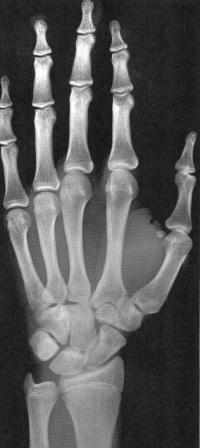

Sexo Masculino

14 anos

15 anos